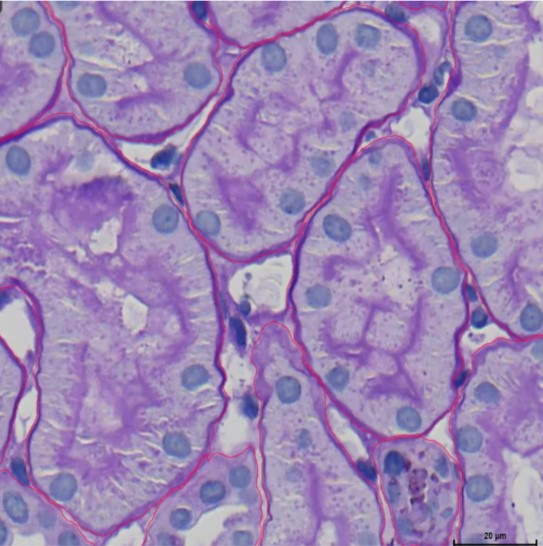

The AI model’s annotations in the provided histological image appear to be of high quality. The red lines accurately trace the boundaries of cellular structures, indicating good alignment with natural edges. The annotations cover most visible structures, suggesting completeness. Consistency is maintained throughout the image, with similar structures being outlined similarly. The clarity is upheld by using thin lines that do not obscure important details, and the annotations follow the contours of the structures specifically, reflecting the model’s capability to recognize fine details. Overall, the annotations are accurate, complete, consistent, clear, and specific.

The annotations produced by the AI model show excellent quality in this close-up photograph. The red lines closely adhere to the cellular structure limits, demonstrating a high degree of precision in identifying the cell borders. It is well aligned with the natural curves, and it seems to have delineated every visible structure, indicating thorough detection. Reliability is ensured by the uniform annotation style, which defines each cell in a comparable way. Thin red lines are used without obscuring interior features to retain clarity. The annotations are detailed, paying close attention to the minute features of the cell borders, suggesting that the model can accurately represent complex changes in cell shapes. All in all, the annotations are precise, comprehensive, coherent, unambiguous, and targeted.

This image appears to be a histological section stained and viewed under a microscope, likely showing tissue structures with cellular and extracellular components. The red lines outline specific areas, probably marking regions of interest, which could be different tissue compartments or specific cellular formations. The quality of the image is clear, with distinct staining allowing for the differentiation of various cell types and structures. The quantity of marked areas suggests a detailed analysis, possibly for diagnostic or research purposes, highlighting numerous regions within the sample. The overall resolution is sufficient to observe cellular details, making it valuable for precise histopathological evaluation.

This picture shows a second dyed and microscope-observed histological slice, most likely at a different magnification or area. The tissue’s different features are indicated by the red outlines. These structures resemble tubules or glandular forms, presumably from a kidney or similar glandular organ. Due to efficient staining, the picture quality is excellent and allows for simple identification of nuclei and other cellular elements. There is also a clear distinction between cellular and extracellular components. The number of indicated structures suggests a careful method of emphasizing particular regions of interest, implying a thorough examination for research or diagnostic reasons. The tissue architecture can be seen in great detail thanks to the exceptional resolution, which makes it an invaluable tool for histopathological analysis.

This image appears to be a microscopic view of a tissue sample, likely stained using a method such as Hematoxylin and Eosin (H&E) to highlight cellular structures. The deep purple areas represent cell nuclei, while the lighter purple areas are the cytoplasm and other tissue components. The red lines overlaying the image indicate that an AI tool has been used to annotate specific structures within the tissue. These annotations typically highlight important regions of interest, such as cell boundaries or areas indicative of pathological changes. The precision of the annotations suggests that the AI model is proficient in recognizing and delineating complex biological structures, which is crucial for tasks like histopathological analysis. The AI’s ability to accurately annotate these features can assist pathologists in diagnosing diseases, ensuring that subtle morphological changes are not overlooked. This combination of AI and histology exemplifies how technology can augment traditional medical practices, leading to more efficient and accurate diagnostics.

As you can see in This image is a microscopic view of a tissue sample stained with Hematoxylin and Eosin (H&E), highlighting cell nuclei in deep purple and cytoplasm in lighter purple. The red lines are AI-generated annotations, accurately outlining cell boundaries and key structures. The precision of these annotations showcases the AI’s capability in histopathological analysis, aiding in disease diagnosis by providing reliable and consistent identification of cellular components. This integration of AI enhances the efficiency and accuracy of medical diagnostics.

This image is a magnified view of a tissue sample stained with Hematoxylin and Eosin (H&E), where cell nuclei appear in dark purple and the surrounding cytoplasm in lighter shades. The red lines overlaying the image represent AI-generated annotations, which precisely mark the boundaries of individual cells. These accurate delineations by the AI demonstrate its high-quality performance in identifying and outlining cellular structures within the tissue. Such detailed and consistent annotations are crucial in histopathological analysis, facilitating the detection of abnormalities and aiding in accurate disease diagnosis. The integration of AI technology in this context significantly enhances the efficiency and reliability of medical assessments.

this image shows tubulus and PTC and how they connected